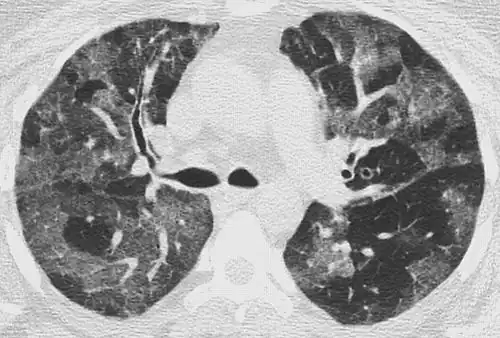

CT image showing crazy paving pattern of ground-glass opacities in both lungs.

The crazy paving pattern may occur when there is both interlobular and intralobular widening. This sometimes resembles a road paved with irregular bricks or tiles. It is typically diffuse, involving larger areas of one or multiple lobes. There are a variety of potential causes, including Pneumocystis pneumonia, late-stage adenocarcinoma, pulmonary edema, some types of idiopathic interstitial pneumonias, diffuse alveolar hemorrhage, sarcoidosis, and pulmonary alveolar proteinosis.[6] COVID-19 has also been shown to occasionally cause GGOs with a crazy paving pattern.[11]

Several studies have described a pattern among initial, intermediate, and hospital discharge imaging findings in the disease course of COVID-19. Most commonly, initial CT imaging reveals bilateral GGOs at the periphery of the lungs. During initial stages, this is most often found in the lower lobes, although involvement of the upper lobes and right middle lobe has also been reported early in the disease course.[16][18] This is in contrast to the two similar coronaviruses, SARS and MERS, which more commonly involve only one lung on initial imaging.[19][20] As the COVID-19 infection progresses, GGOs typically become more diffuse and often progress to consolidation.[11][18] This is sometimes accompanied by the development of a crazy paving pattern and interlobular septal thickening.[18] In many cases the most severe pulmonary CT abnormalities occurred within 2 weeks after symptoms began.[17] At this point, many individuals begin showing resolution of consolidation and GGOs as symptoms improve. However, some patients have worsening symptoms and imaging findings, with further increase in septal thickening, GGOs, and consolidation. These patients may develop lung "white-out" with progression to acute respiratory distress syndrome (ARDS) requiring treatment escalation.[17][21]